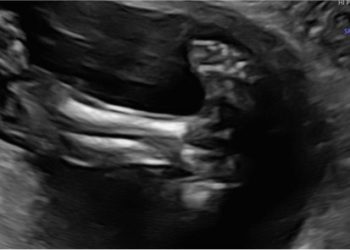

Per il mese di Dicembre SIEOG Giovani presenta il Webinar sullo screening delle cardiopatie congenite nel primo trimestre. La registrazione...